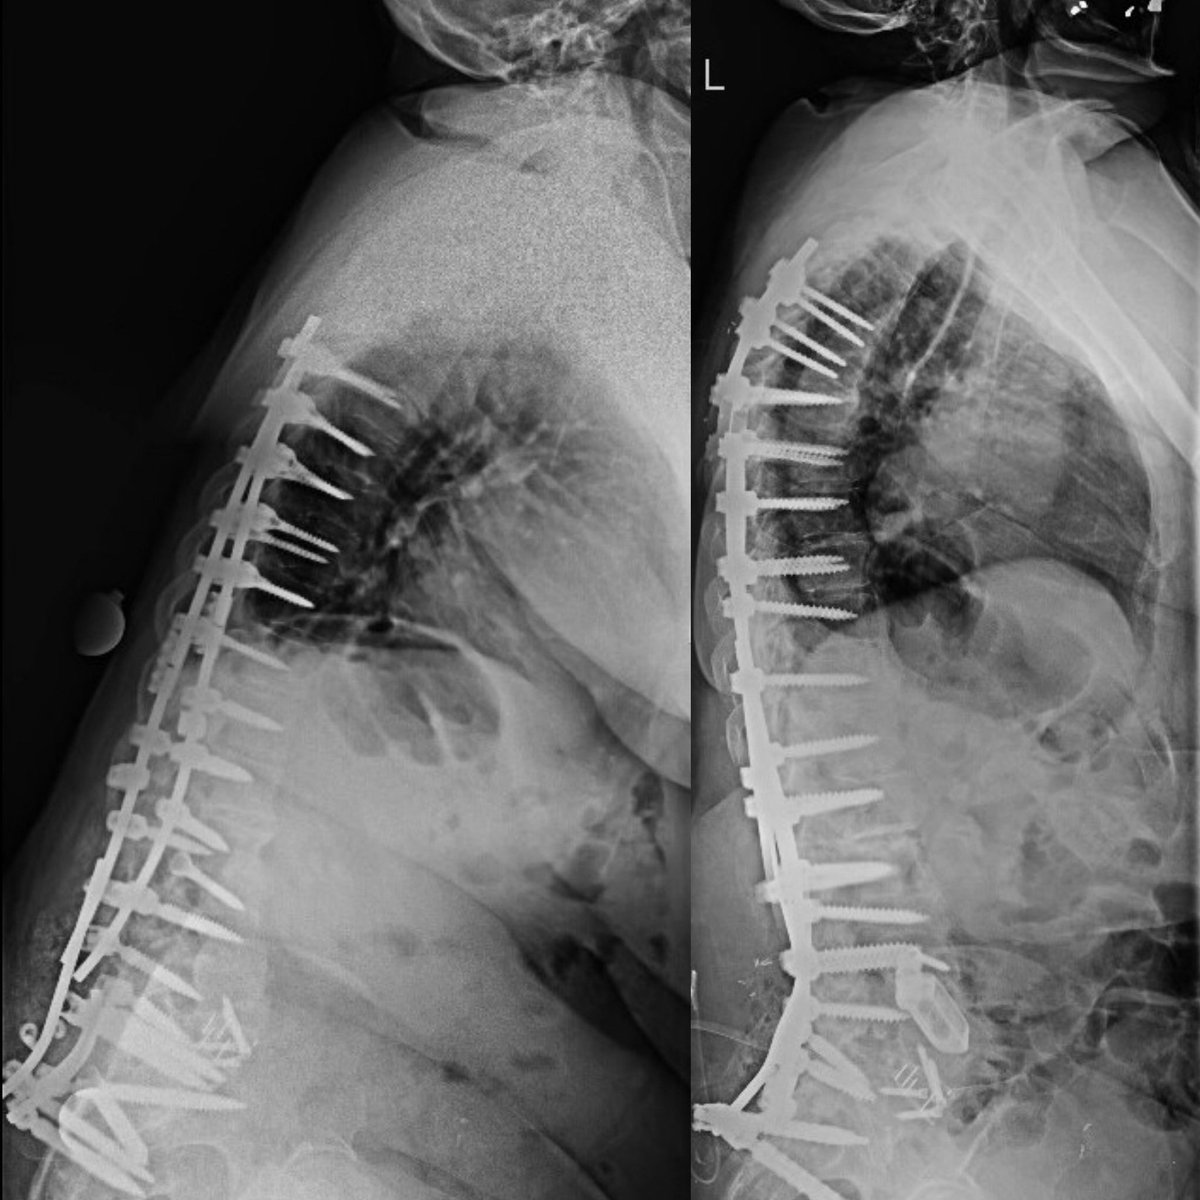

@docclift

Bill Clifton, MD

10 months

Honored to present at the 2025 Masters in Advanced Spinal Deformity meeting. So great to learn from my spinal deformity colleagues continuing to push the field forward in safety, indications, and outcomes! #MedX #scoliosis @spinesection @ClevelandClinic @CleClinicNS